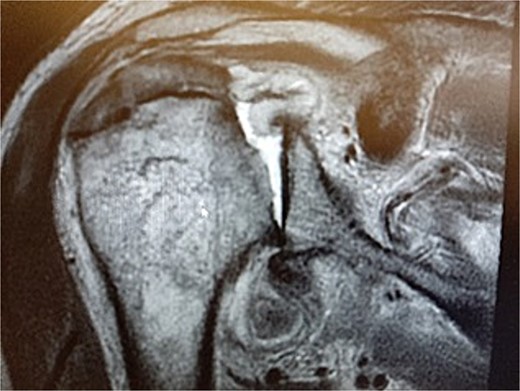

During the outpatient follow-up visit at the Orthopedic Clinic, ~10 weeks after the accident, a physical examination of the patient was conducted, which included shoulder X-ray imaging. The examination revealed severe pain in the right shoulder and a significant limitation in the mobility of the joint (results summarized in Table 1). The above enforced the decision of expanding the imaging diagnostics to look for fractures within the humeral head; hence, computed tomography (CT) and magnetic resonance imaging (MRI) examinations of the right shoulder were carried out. Additional imaging studies revealed a depression fracture of the humeral head covering 2/3 of the articular surface with posterior subluxation of the right shoulder joint. The examination also revealed that the continuity of the tendons of the rotator cuff muscles has been preserved.

MRI images can be found in Figs 3 and 4, and CT images in Fig. 5.